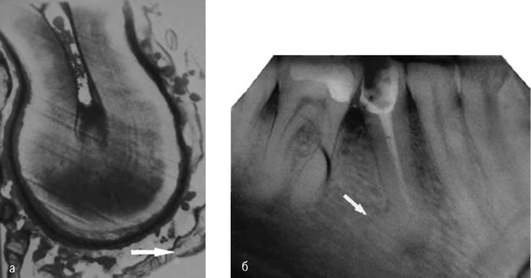

Форма и размер гиперцементоза могут быть различными как на рентгенограмме (рис. 13-2), так и на удалённых зубах (рис. 13-3, см. цв. вклейку).

Следствием воспалительного процесса может быть резорбция альвеолы костной ткани и цемента корня (рис. 13-4).

image

Рис. 13-2. Гиперцементоз: а - гистологический срез; б - рентгенограмма зуба 45

Рис. 13-4. Резорбция альвеолы костной ткани и цемента корня зубов: а - зуба 22; б - зубов 31 и 41